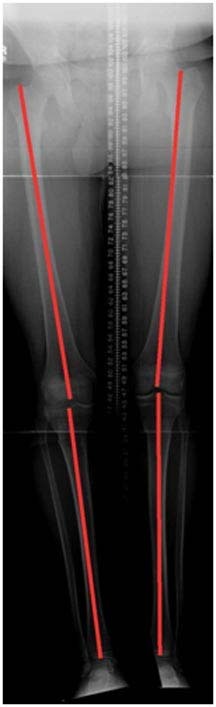

3.Using a specialized computer program, a computerize preoperative plan is created correcting the deformity and providing us with a guide to achieve complete correction of the deformity.